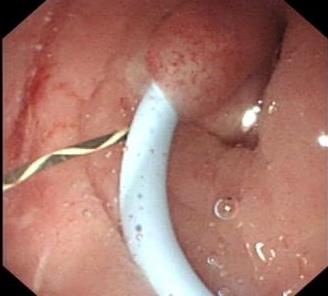

摘要:目的 探讨软式内镜辅助逆行性输尿管导管置入术,对Bricker回肠膀胱术后,输尿管回肠吻合口狭窄即刻再通的疗效。方法 回顾性分析2016年11月-2022年10月该院收治的17例Bricker回肠膀胱术患者的临床资料,共28处输尿管回肠吻合口狭窄,均行软式内镜辅助逆行性输尿管导管置入术治疗。结果 所有患者的总手术时间均 < 50 min。经内镜治疗成功再通的有21处。中位住院时间为6(4.75,8.50)d。28处输尿管回肠吻合口狭窄中,21处内镜下即刻再通成功(左侧10处,右侧11处),7处内镜下即刻再通失败(左侧4处,右侧3处)。21处内镜下即刻再通成功包括:单纯性逆行性置入输尿管导管15处,内镜下输尿管回肠吻合口扩张、网篮取石和逆行性支架置入1处,超细内镜下逆行性输尿管支架置入术3处,十二指肠镜下逆行性输尿管支架置入术2处。17例患者,输尿管支架尿液引流通畅,代膀胱回肠及输尿管回肠吻合口均有不同程度擦伤和少量出血,未发生迟发性出血、穿孔、严重泌尿系感染、支架堵塞和移位等严重并发症。结论 软式内镜辅助逆行性输尿管导管置入术,对输尿管回肠吻合口狭窄的即刻再通,安全且有效。值得应用于临床。